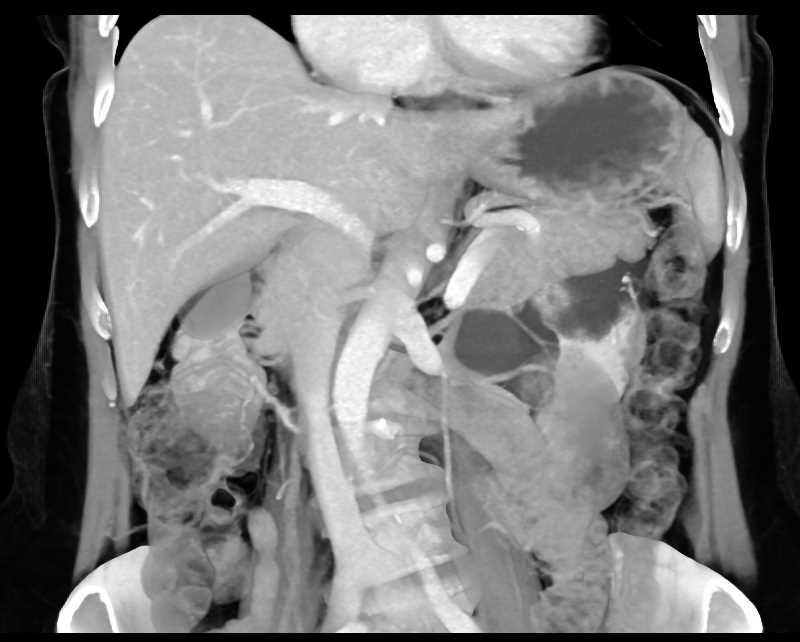

Parapelvic Cysts Left Kidney